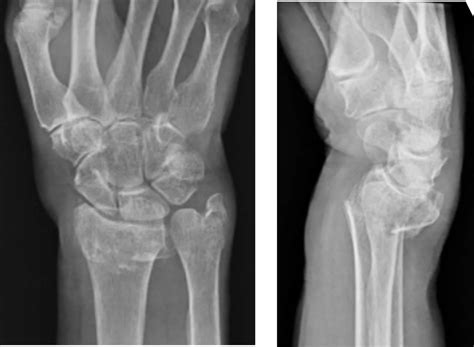

Distal Radius Fracture Sudden onset after trauma. Sharp pain, severe swelling, bruising.

DRUJ Instability Bone shifts during rotation. Clicking, popping sensation, instability.

If you notice your wrist bone sticking out and it is accompanied by functional limitations, it is time to consult an orthopedist or a physical therapist. A medical professional will typically perform a physical examination to check for stability and may order diagnostic imaging, such as an X-ray, to rule out fractures, ligament tears, or severe arthritis.